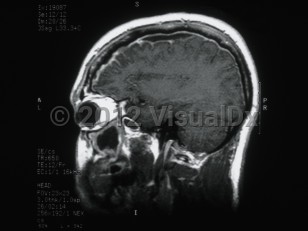

Subdural empyema is a collection of pus in the space between the dura and the arachnoid. Infection of the paranasal sinuses is a risk factor for cranial subdural empyema, as the infection can spread to the space by way of emissary veins. Contiguous spread of infection from osteomyelitis of the skull, meningitis, mastoiditis, or otitis media are also possible. Other etiologies include trauma, seeding of an existing subdural hematoma, or postoperative infection. These infections are typically polymicrobial.

Hematogenous seeding of the space is more likely to result in spinal subdural empyema. This location is less common, accounting for less than 5% of subdural empyema. Staphylococcus aureus is often implicated in infections in this location. Patients may present with fever, headache, and altered mental status (or some combination of these symptoms). Focal neurological signs and seizures may also be present. Magnetic resonance imaging (MRI) with contrast is the diagnostic test of choice.

Treatment is with a combination of surgical decompression and antibiotic therapy. Complications include cerebritis, cerebral abscess formation, and venous sinus thrombosis. Morbidity and mortality in subdural empyema is directly related to delay in therapy.